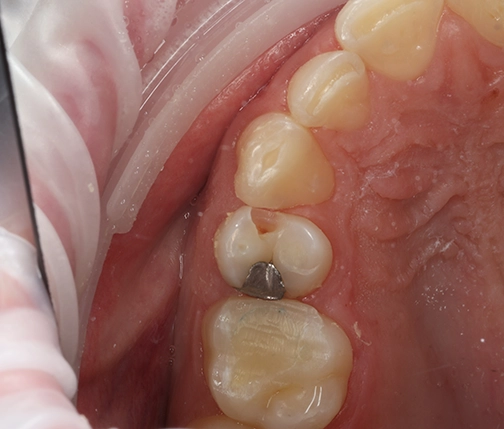

Intraoral camera and NIRI technology (Near Infra-Red Imaging) images offer additional data to technicians

Using the digital protocol with practices equipped with iTero scanners, we can gather all the data needed to understand the doctor’s needs. We now receive more information via the iTero-exocad Connector™, along with detailed prescriptions. This new integration enables us to access high-definition intraoral and NIRI technology (Near Infra-Red Imaging) images offering us more information than we ever had before.

For instance, problems such as soft tissue covering marginal areas can be readily identified. The enhanced visual clarity empowers us to rectify distortions independently, without direct communication with dentists. Now that we’ve got it, I would like to request it from all the clients we work with.